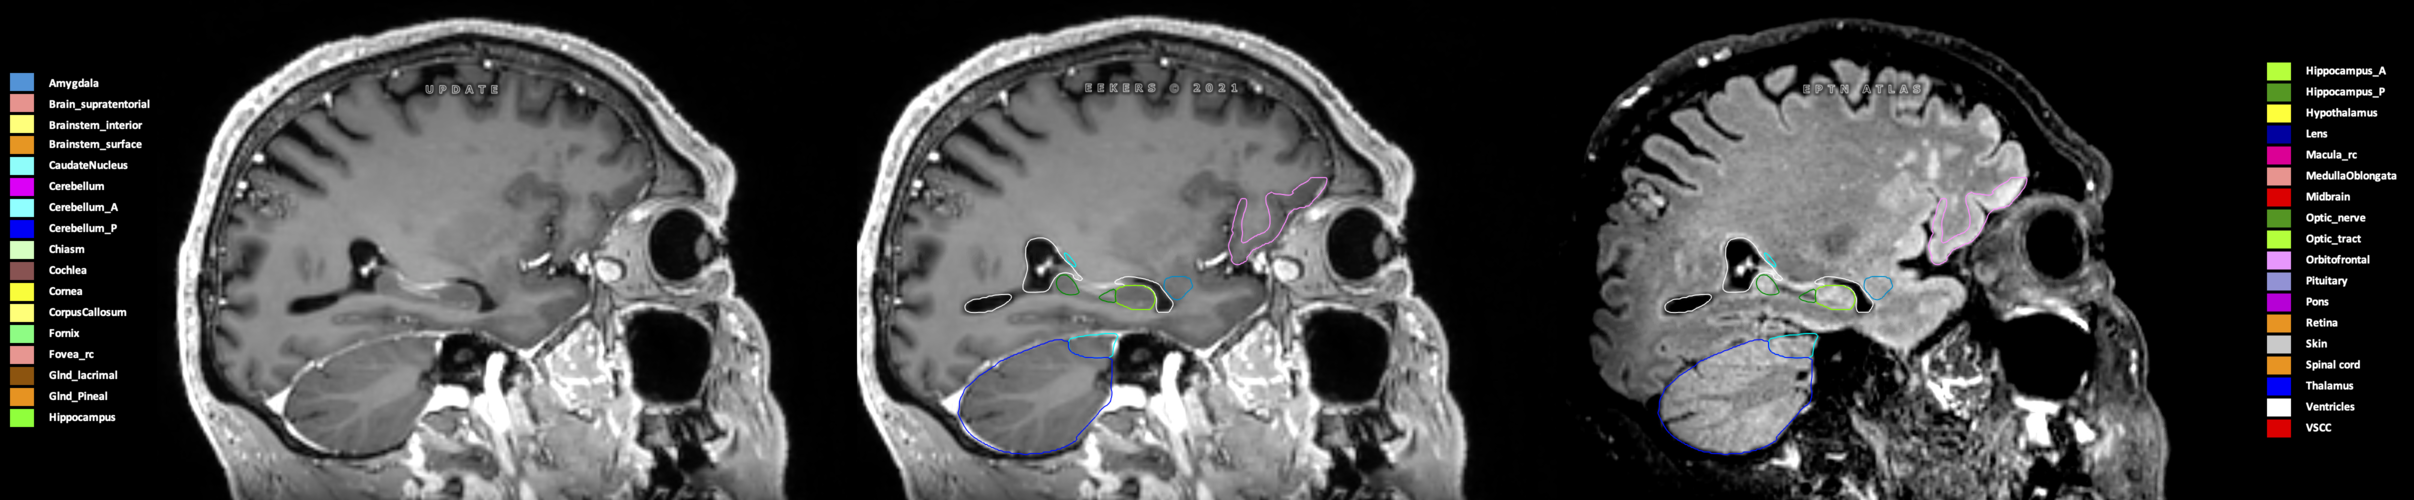

Included are all OARs known to be relevant for radiation-induced toxicity in neuro-oncology: brain, brainstem (midbrain, pons, medulla oblongata), chiasm, cerebellum (anterior & posterior), cochlea, cornea, hippocampus (anterior & posterior), hypothalamus, lens, lacrimal gland, optic nerve, pituitary, skin, and vestibular & semicircular canals. To further facilitate research on cognition, vision and radiological changes after irradiation of the brain, potential clinically-relevant OARs are included: amygdala, caudate nucleus, cerebellum (anterior & posterior), corpus callosum, fornix, macula, optic tract, orbitofrontal cortex, periventricular space (PVS), pineal gland, and thalamus.

Three-dimensional delineation of the 25 consensus OARs for neuro-oncology are shown on CT (WW/WL 120/40, 3000/600), 3T MR images, (T1Gd, T2FLAIR 1mm) and 7T MR (MP2RAGE 0.7 mm). All are presented in transversal, sagittal and coronal view.